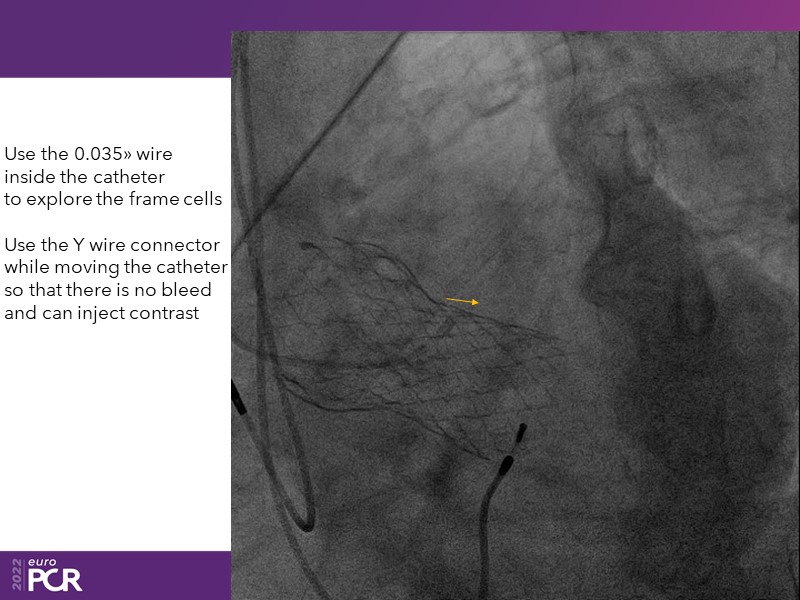

Consult this session to learn how to contribute to streamlined pre- and post-TAVI patient pathways, to discover updates on the optimised TAVI procedure and appreciate the variances in different valve designs and the long-term patient outcomes, as well as to discuss the right time of PCI in TAVI patients (steps on the procedure).

- To discuss the right time of PCI in TAVI patients (steps on the procedure)